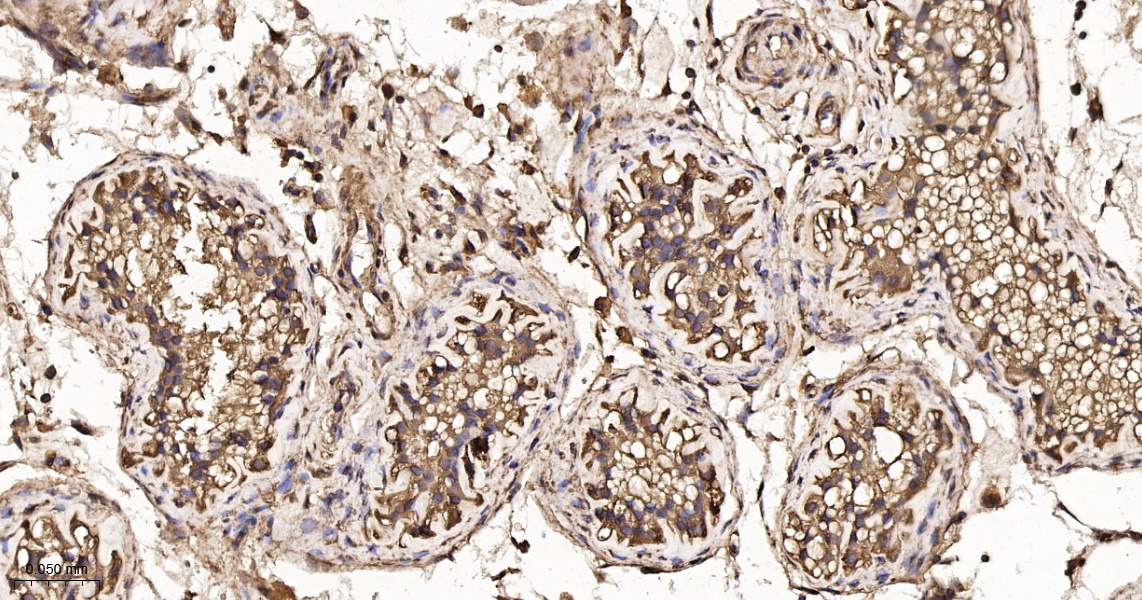

• IHC-P

IHC-P IHC-P1:100-500